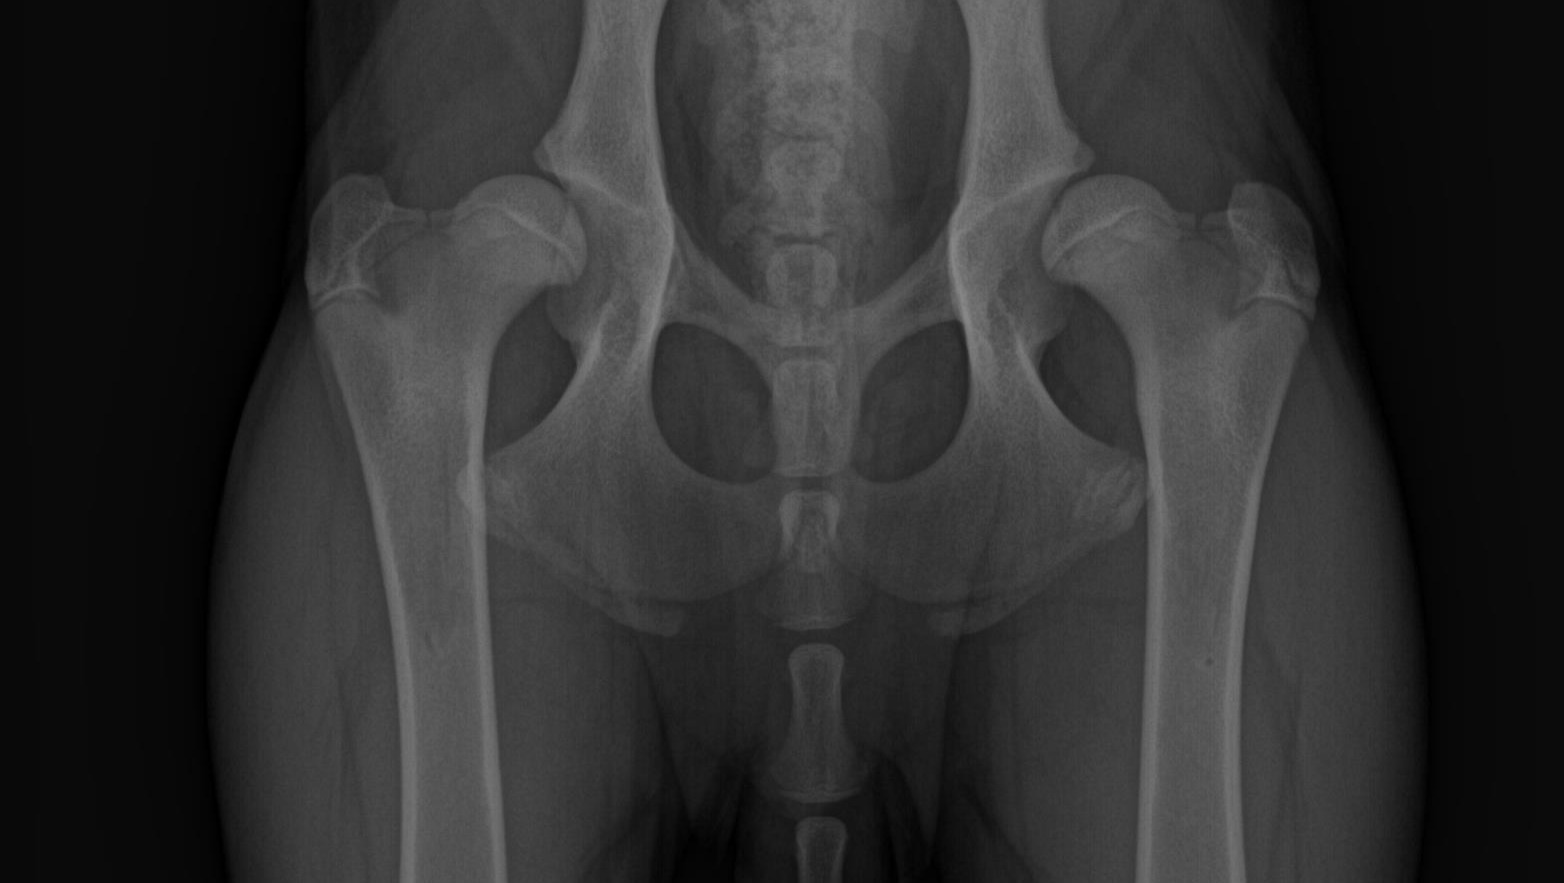

Un paio di mesi fa i miei genitori (non sono i miei veri genitori: sono solo due che mi hanno raccolto un giorno e non mi hanno più lasciato andare) si sono accorti che camminavo in modo bizzarro. Mia madre dice sempre che cammino come “due persone in un costume da cavallo”. Così mi hanno portato dal veterinario e hanno scoperto che i miei veri genitori mi hanno trasmesso la displasia dell’anca. Bilaterale e molto molto grave. Nessuno sapeva molto di loro perchè sono stato ritrovato con mio fratello sul ciglio della strada. Anche lui ha la displasia. Ma anche questa è un’altra storia.

Non abbiamo un preventivo ufficiale da caricare perchè non siamo ancora certi della cifra esatta che dovremo spendere. Il costo della protesi d'anca varia da 3300 a 3800 euro più IVA per anca (in funzione delle dimensioni degli impianti) e comprende gli impianti in titanio, l'intervento, le radiografie post-operatorie ed il ricovero di 24 ore con le relative cure. Eventuali radiografie pre-operatorie per cani non già sottoposti ad una visita preliminare della clinica che lo opererà (che è il nostro caso), saranno da conteggiare a parte.

Scopriremo pertanto il costo delle protesi la mattina stessa dell'intervento: andrà dai 4.026 € ai 4.636 € per gamba, per cui in totale da 8.052 a 9.272 € più il costo delle radiografie pre operatorie che non conosciamo ma che nella nostra esperienza varia tra i 200 e i 350 euro.

My mom said I walk like “two people in a horse costume”. So they took me to the vet and found out that my real parents gave me hip dysplasia. Bilateral and very bad. Nobody knew much about them because I was found with my brother on the side of the road. He has dysplasia too. But this again is another story.